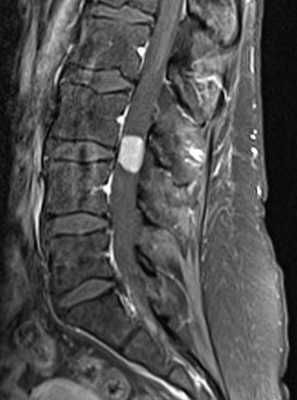

Локальная киста обычно наблюдается в месте наибольшего сдавления спинного мозга кистой или грыжей диска. Чаще они наблюдаются при травмах шейного отдела позвоночника. Киста при МРТ позвоночника имеет типичный ликворный сигнал в спинном мозге и может быть окружена зоной миеломаляции.

МРТ шейного отдела позвоночника. Локальная киста. Т2-взвешенная сагиттальная МРТ.

Атрофией считается уменьшение передне-заднего измерения спинного мозга по результатам МРТ меньше 7 мм в шейном отделе и меньше 6 мм в грудном. Участок атрофии при МРТ может быть локальным или протяжённым, если он распространяется более чем на 2 позвонковых сегмента. Граница атрофии на Т2-взвешенных МРТ нечёткая. Распространённая атрофия является типичным отдалённым последствием спинальной травмы.

МРТ шейного отдела позвоночника. Компрессия и атрофия спинного мозга. Т2-взвешенная сагиттальная МРТ.